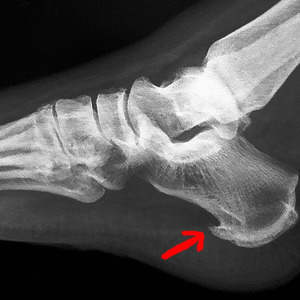

Причиной таких жалоб становится появление костного выроста (остеофита) в месте соединения пяточной кости и ахиллова сухожилия на фоне хронического воспаления. У многих возникает вопрос о том, что делать с такой проблемой и как убрать шип на пятке. В статье пойдет речь о лечении пяточной шпоры в домашних условиях и народными средствами.

Появлению пяточной шпоры предшествует длительная воспалительная реакция, которая изначально развивается в мягких тканях сухожилия, а затем переходит на связочный аппарат и кости.

Костные структуры реагируют на повреждение усилением регенеративных процессов, что приводит к появлению на них наростов. В результате образуется костный вырост, который и становится главной причиной болевых ощущений.

Формирование остеофита происходит при нарушениях метаболизма пуринов (подагре), в пожилом возрасте, при ношении неподходящей или неудобной обуви, хронических заболеваниях опорно-двигательного аппарата (плоскостопии), избыточной массе тела и т.д.